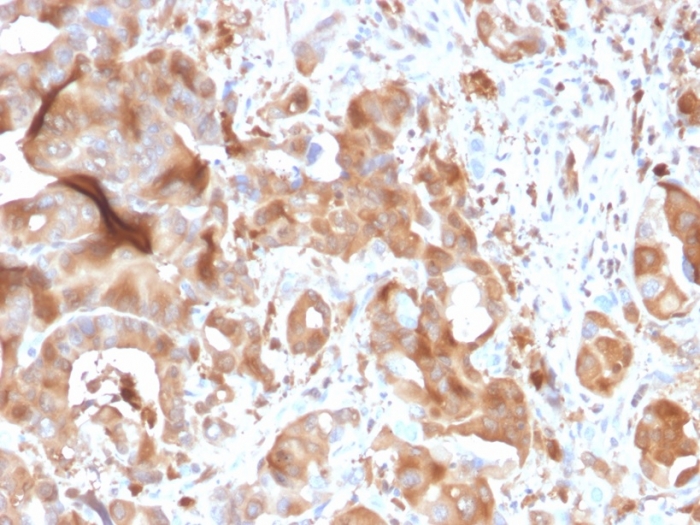

img

Formalin-fixed, paraffin-embedded human hepatic carcinoma stained with FABP5 Mouse Monoclonal Antibody (CPTC-FABP5-3).